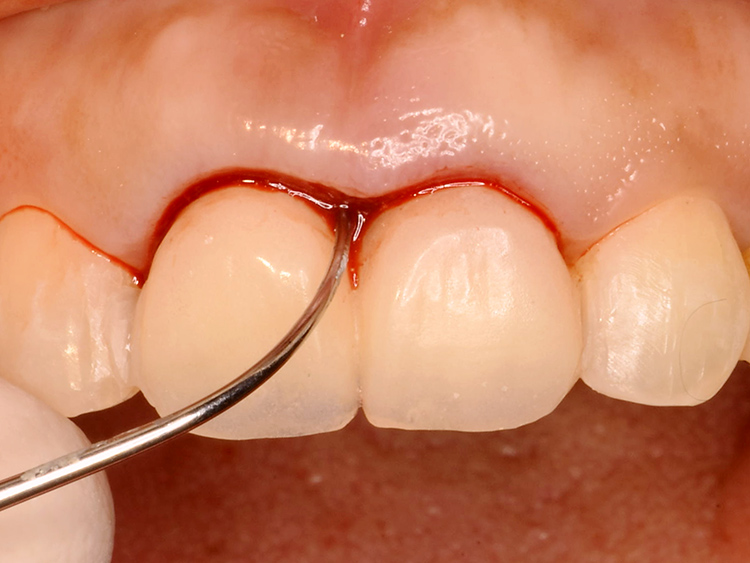

歯根破折部に隣接する歯肉は、赤く炎症を起こし損傷していました。

歯肉の健全な厚みや歯根への付着が失われ、細菌感染に対するバリア機能も低下していました。せっかく歯を保存し修復できたとしても、その後に虫歯や歯周病を再発させては意味がありません。

最終的なセラミックス冠を装着する前に、仮歯の形態を調整しながら、健全な歯周組織の回復を誘導します。